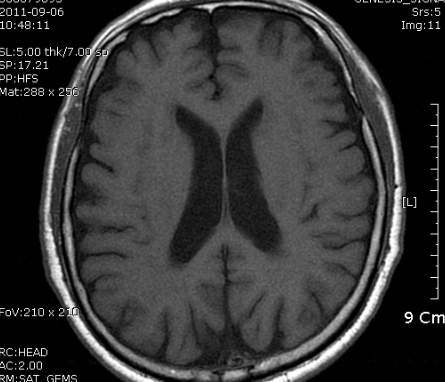

B MRI 촬영 결과는 좌측의 corona radiata, Lt temporo-occipital lobe 의 subcortical area 의 optic radiation 부위를 비롯한 여러 군데 점상 병변. N/S 정주하고 Aspirin 투여 시작, 혈압약은 지속 투여, SBP 160정도로 유지.

촬영 결과는 좌측의 corona radiata, Lt temporal lobe는 anterior choroidal artery 영역입니다.

좌측사진은 PCA 영역. 우측사진은  AchA 영역의 post. periventricular corona radiata (Stroke 4ed p199, Fig 9-3 과 동일)